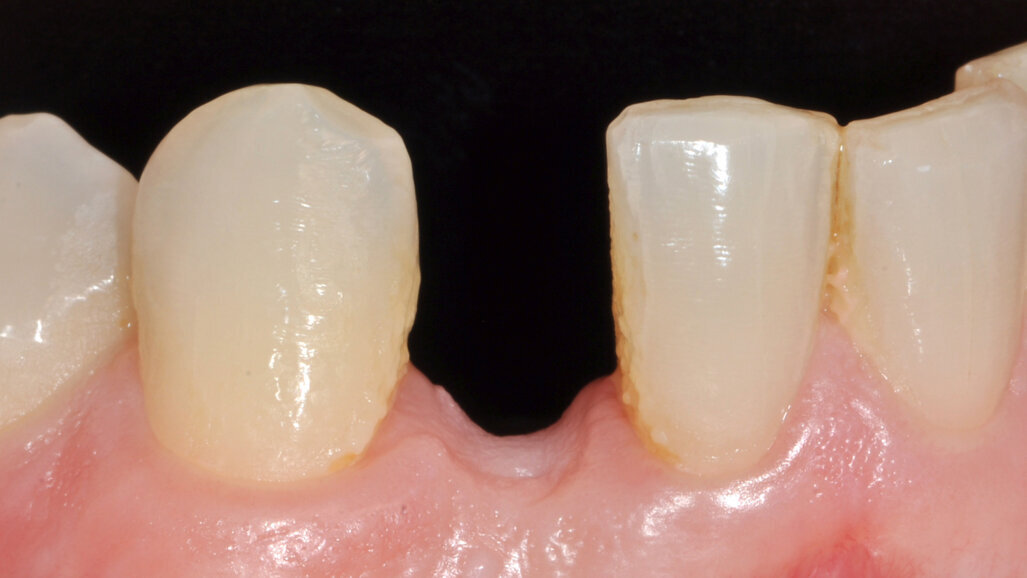

Definitivní náhrada

Pacient byl objednán na kontrolu týden po chirurgickém zákroku. V té době bylo dosednutí provizorní náhrady shledáno uspokojivým (obr. 11). Obrázek 12 zachycuje digitální plánování abutmentu Atlantis Crown Abutment ze zirkonu s adekvátním prostorem pro vrstvy keramiky. Definitivní náhrada byla vyrobena v zubní laboratoři s ohledem na dosažení harmonie se sousedními zuby (obr. 13). Byl také vytvořen prostor pro aproximální papilu. Abutment kotvený šroubkem s lingválním přístupem lze vidět na obrázku 14. Provizorní náhrada byla vyměněna za definitivní (obr. 15). Subgingivální část abutmentu poskytla oporu měkkým tkáním a byl zajištěn prostor pro mezizubní papilu. Atlantis Crown Abutment byl dotažen točivým momentem 25 Ncm (obr. 16). Lingvální přístup ke šroubku byl nejprve zakryt výplňovým materiálem (PTFE) a poté kompozitem. Následně byl pořízen další RTG snímek implantátu s upevněným definitivním abutmentem Atlantis Crown Abutment (obr. 17). Na obrázku 18 lze vidět konečný výsledek s definitivní náhradou, na němž je patrný adekvátní obrys měkkých tkání a vyplnění aproximálního prostoru. Keramika rovněž dokonale napodobila odstín sousedních zubů.